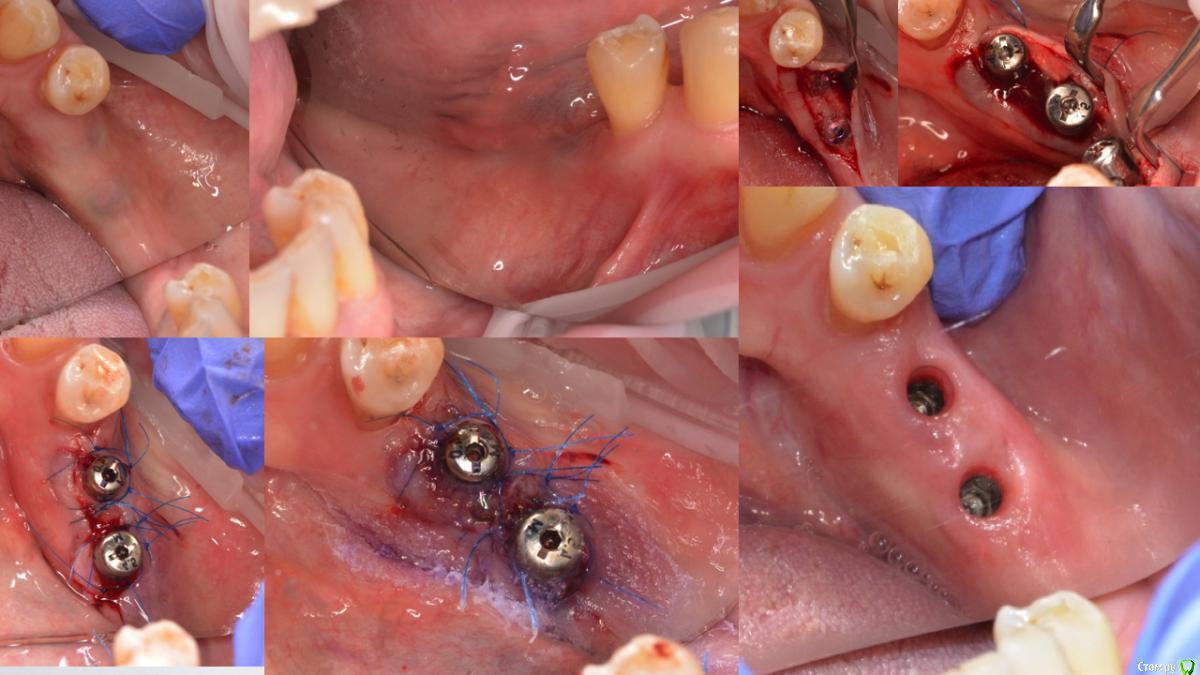

doktorenok Опубликовано 21 апреля, 2015 Поделиться Опубликовано 21 апреля, 2015 Ситуация следующая: в декабре 2013г проведена имплантация в 3 сегменте одномоментно с вертикальной аугментацией с применением мембраны Цитопласт (изначально над каналом было 4-5 мм). В июне 2014г раскрытие имплантов без манипуляций с мягкими тканями, ортопед вернул работу хирургу с просьбой сделать ткани прикрепленными. В июле 2014 г проведена пластика мягких тканей с применением Мукографта, направлен к ортопеду. Ортопед вернул хирургу с жалобами, что все подвижно. В ноябре 2014 г проведена операция углубления предверия по Казаньяну. На сегодняшний день ортопед опять недоволен, привел пациента ко мне и просит поправить ситуацию. Ситуация следующая: кератинизированной нет вообще, вестибулярно ткани очень тонкие, но прикрепленные, посередине между имплантов при натяжении щеки -слизистый тяж почти до середины гребня, язычно - ни прикрепленной, ни кератинизированной . Как бы Вы поступили? Варианты, которые вижу я:1. Оставить как есть, Пациент измучен. Но думаю будет периимплантит в ближайшем будущем.2. Вестибулярно- пересадка СДТ, язычно- деэпителизированный СДТ под расщепленный лоскут..3. Вестибулярно ничего не трогать, а язычно-деэпителизированный СДТ под расщепленный лоскут.4. Взять пошире СДТ , деэпителизировать его , надеть на формирователи и под расщепленный лоскут и язычно и вестибулярно.5. Заглушить импланты, пересадить СДТ. После приживления часть отдать на язычную сторону, а вестибулярную часть сместить апикально, или еще подсадить. Сама склоняюсь к 3 варианту.Проблема в том, что расщепить ткани вестибулярно будет сложно, они очень тонкие , будут рваться и разлезаться, и вестибулярно все очень бледное и в рубцах, то есть с кровоснабжением там плохо после нескольких хирургических вмешательств., боюсь получить некроз СДТ.Язычно - будет ли какой то результат от подсаженного деэпит. СДТ , учитывая тот факт, что кератинизированной нет вообще.На фотографиях все выглядит почему-то лучше, чем есть на самом деле. Фотограф я начинающий Поделитесь пожалуйста, кто как поступает в подобной ситуации? Ссылка на комментарий